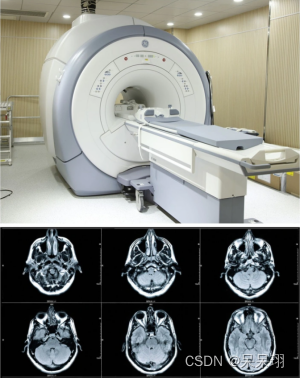

4. MRI(磁共振成像)

1. 概念:MRI利用强磁场和无损的无线电频率来生成身体内部的详细图像。MRI提供高对比度和解剖细节。

2. 优点:

- 高对比度:MRI图像具有高对比度,有助于检测软组织结构和异常。

- 无辐射:MRI不使用X射线,无辐射风险,适用于孕妇和儿童等敏感人群。

- 可提供多种图像序列:MRI可以提供多种不同的图像序列,以突出不同的组织和病变。

3. 缺点:

- 相对较慢:MRI扫描时间较长,患者需要保持静止。

- 对患者协作要求高:MRI对患者协作度要求较高,如需保持静止和忍受闭合式设备。

- 对部分人群有限制:MRI对携带金属物体、心脏起搏器等患者的使用有限制。

4. 应用:MRI常用于检查脑部、脊柱、关节、软组织等。